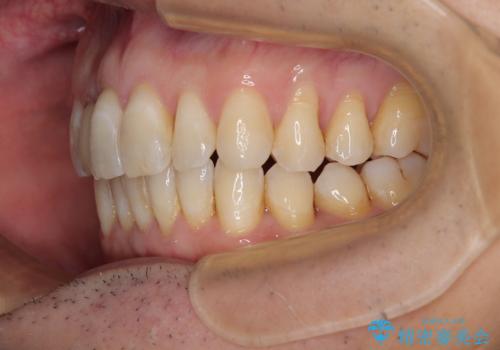

前歯のデコボコを治したい インビザラインによる矯正治療

- 前歯のデコボコを気にして来院された患者様です。

目立たない装置で手軽に治したいとのことで、インビザラインにて矯正治療を行うこととしました。

前歯のクラウンは変色が著しいため、矯正治療後にオールセラミッククラウンにて補綴治療を行うこととしました。

担当医としてはもう少し前歯のデコボコを改善したいところでしたが、患者様としては十分に満足いく歯列であり、マウスピース矯正に飽きてしまったとのことで、治療終了となりました。